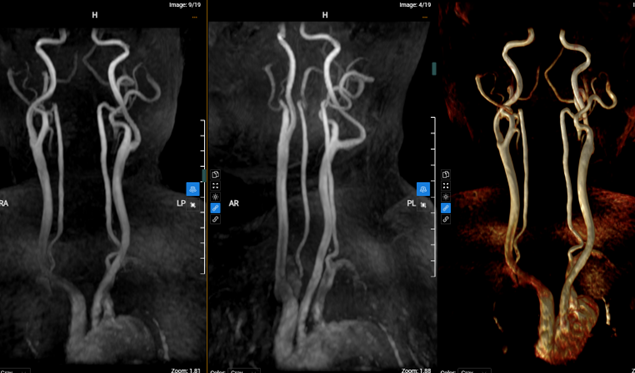

Giãn động mạch cảnh

Giãn động mạch cảnh và các vấn đề về tim mạch khác cũng có thể góp phần khiến động mạch đập nảy và mạnh bất thường.

Khi bị mạch corrigan, bạn sẽ thấy động mạch cảnh hoạt động bất thường, biểu hiện dưới dạng giật nẩy mạnh, chuyển động giãn và xẹp nhanh. Bên cạnh đó, người bệnh có thể gặp phải một số triệu chứng khác đi kèm như nhịp tim yếu, các vấn đề về van tim (hiện tượng thu hẹp van tim hoặc rung van), nghe được tiếng tim,...